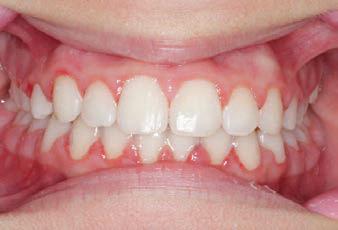

Carriere Motion 3D Appliance

Fastrack your orthodontic treatments. Save 6 months or more.

The SAGITTAL FIRST™ Philosophy is a time-tested approach that standardises, simplifies, and shortens Class II and Class III treatment times. It employs the Carriere Motion 3D Appliance to treat the AP dimension at the beginning of treatment before placing brackets or aligners. By resolving the most difficult part of treatment first, you can achieve a Class I platform in 3 to 6 months, shortening total treatment time by a minimum of 6 months1. You know how excited patients and parents become when you mention shorter treatment times.

CLASS II DIV.1 - Marra

PROVIDED BY: DR. LUIS CARRIÈRE

INITIAL - 4/4/18

PROGRESS 1 - 26/9/18 - Class I platform accomplished in 5.75 months with Motion 3D COLOR Appliance

PROGRESS 2 - 26/9/18 - Placement of the SLX 3D Clear Brackets

[CONTINUED ON NEXT PAGE]

with M-ONE .015 Cu Nitanium 27°

PROVIDED BY: DR. LUIS

PROGRESS 3 - 30/10/18 - With M-TWO .020 x .020 Cu Nitanium 35° archwire

PROGRESS 4 - 27/11/18 - 3 links power chain: 5, 4, bypass 3 to crimp hooks

PROGRESS 5 - 13/3/19 - With M-TWO .020 x .020 Cu Nitanium 35° archwire

PROGRESS 6 - 1/8/19 - With M-THREE.019 x .025 Beta Titanium wire

52 HENRY SCHEIN ORTHODONTICS

FINAL - 10/10/19 - Appliances removed AFTER

PROGRESS 7 - 10/10/19 - Final day in SLX 3D Clear Brackets BEFORE